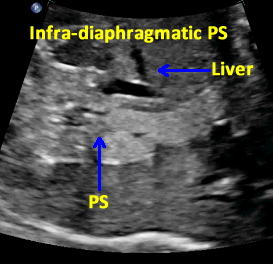

Infra-diaphragmatic Pulmonary Sequestration (PS)

Above. Infra-diaphragmatic Pulmonary Sequestration (PS). Transverse view demonstrates homogeneous, echogenic mass adjacent to the liver and below the diaphragm.

Above. Infra-diaphragmatic Pulmonary Sequestration (PS). Transverse view. Slightly larger image demonstrates homogeneous, echogenic mass adjacent to the liver and below the diaphragm, and in close approximation to the abdominal aorta.

Above. Infra-diaphragmatic Pulmonary Sequestration (PS). Longitudinal view shows the same basic homogeneous, echogenic nature of the mass.

Above. Infra-diaphragmatic Pulmonary Sequestration (PS). Color Doppler indicates the aorta to be the origin of the feeder vessels to the mass.